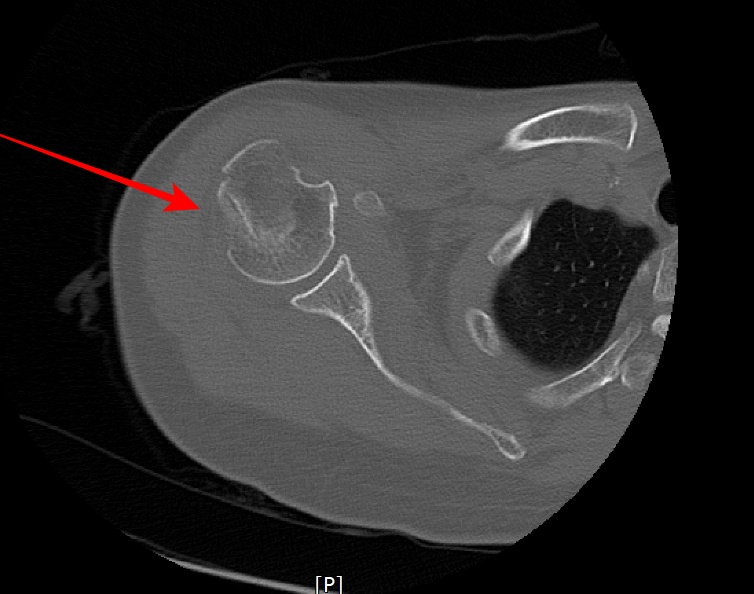

2022.06.04 CT SCAN

- F/50대

- 어제 넘어짐

-velpeau bandage 상태

- Rt Shoulder CT

- surgical neck Fx 의심 되어 검사 의뢰됨.

- 오른쪽 어깨에 velpeau bandage를 한 상태로 통증이 있는 상태였다.

- shoulder 전체를 포함하여 scan 하였다.

- axial 영상을 획득 후 MPR로 재구성하였다.

- 붉은색 화살표가 골절된 부위다.

displaced neck fracture of humerus with impaciton

입원 후 수술예정이다.